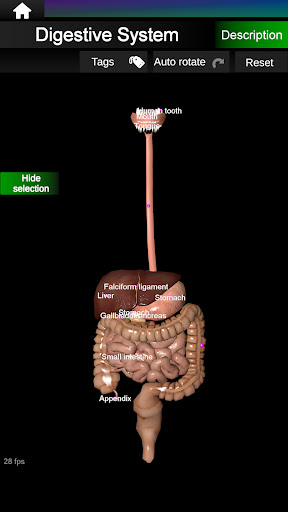

* Digestive system, including the stomach, small intestine, large intestine, and an animation of this system.

* Easy to access and navigate (zoom, 3D rotation).

* Hide or show information.

* Descriptions of each organ.